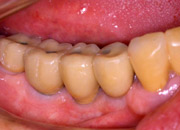

CASE.1(前歯部にインプラントを埋入した症例)